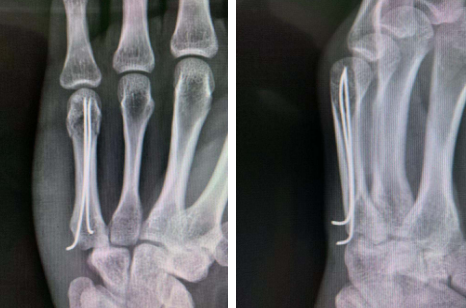

手术采用“顺行穿针内固定”治疗骨折固定情况

熊祖国医生介绍:掌骨颈骨折多见于青少年,因为处于青春期的孩子容易冲动,生气后用拳击打硬物导致骨折。对于这类骨折,采用“顺行穿针微创治疗”效果好,且外形美观。手术方式中克氏针(俗称“钢针”)不经过任何关节,钢针的尾部短小、微创方式进行,对患者损伤小,避免了因钢针尾部外露而造成的钉道感染;固定钢针不影响手部任何关节活动,利于早期功能锻炼,同时对生活影响也很小。